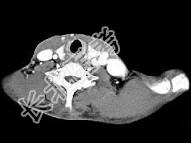

- 单项选择题男,46岁, 外伤后左下颈搏动性肿块,CT如图所示, 最可能的诊断是 ( )

A、左颈部血管瘤

B、左颈动脉体瘤

C、左颈静脉球瘤

D、左颈总动脉假性动脉瘤

E、左颈部动静脉畸形